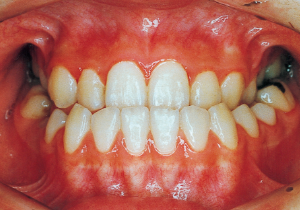

2 After Phase 2 Treatment 5-9-’92

13 5-21-’90 At Phase 2 Treatment

16 5-9-’92 After Phase 2 Treatment

First Phase treatment: Treatment continued for a long period of 2 years and 5 months, from age 8 years and 6 months to age 10 years and 11 months.

Afterwards, follow-up was conducted, but based on the growth pattern, surgical intervention was determined necessary, and the patient entered a period of regular observation.

Regular Observation: 8 years from 10 years 11 months to 18 years 11 months